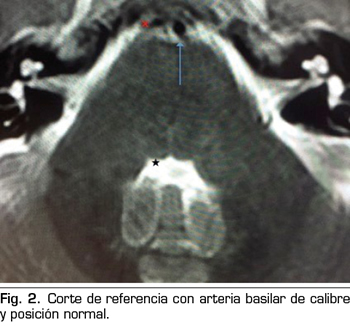

Se hace RM a los 10 días de la aparición de la diplopía objetivando un discreto agrandamiento, elongación y desplazamiento lateral derecho de la arteria basilar, con probable compromiso de espacio en la emergencia de la porción cisternal del VI par derecho (Figuras 1 y 2).

La parálisis del VI PC asociada a CPPD es un diagnóstico por exclusión que requiere la consideración de otras anormalidades neurológicas y oftalmológicas (3). Si la parálisis del VI PC ocurre dentro de las 3 primeras semanas tras la PDA y es precedida de una CPPD, es probablemente consecuencia de la PDA (4). La imagen de la RM puede revelar signos de hipotensión intracraneal, incluyendo engrosamiento meníngeo, colecciones de líquido subdurales y desplazamiento cerebral caudal (11). Estos hallazgos son debidos a la hipotensión intracraneal, sin embargo, no son específicos de la parálisis del VI PC (11). En nuestro caso, la RM no aportaba ninguno de estos signos, pero lo que sí reveló fueron datos de probable compromiso de espacio de una estructura neurológica (emergencia del VI PC derecho) por una estructura vascular (arteria basilar en nuestro caso), planteando el diagnóstico diferencial con un síndrome de compresión neurovascular. El síndrome de compresión neurovascular es definido como el contacto directo con irritación mecánica de los PC por vasos sanguíneos (7). Varios autores han comunicado casos de parálisis unilateral del VI PC, asociada con el contacto neurovascular entre el VI PC y la arteria vertebral o basilar en la RM (6).